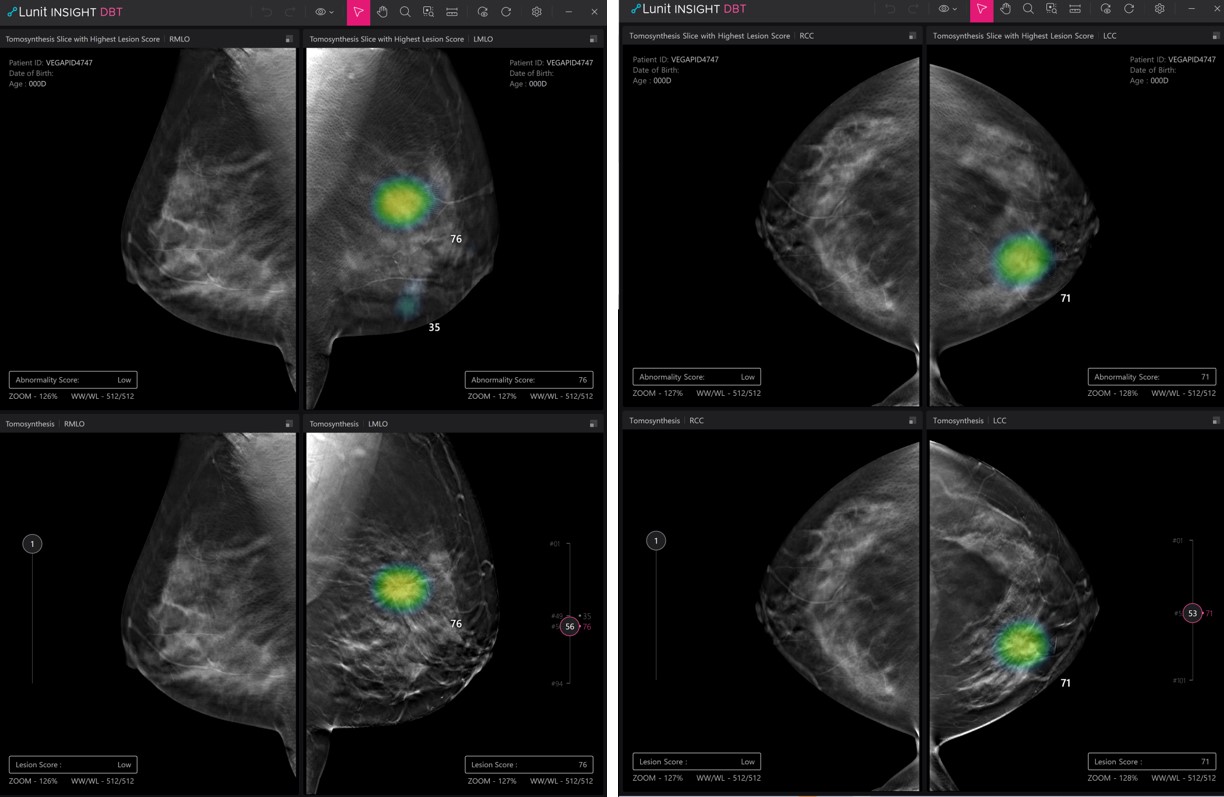

Lunit INSIGHT DBT Demo

According to the company, its AI solution for DBT is called ‘Lunit INSIGHT DBT’, which can accelerate reading by handpicking the 3D slice image with suspicious lesions among multiple images. Its solution for CT is ‘Lunit INSIGHT Chest CT’, which AI automatically generates the location, type, volume, and axial diameter of the detected nodule.